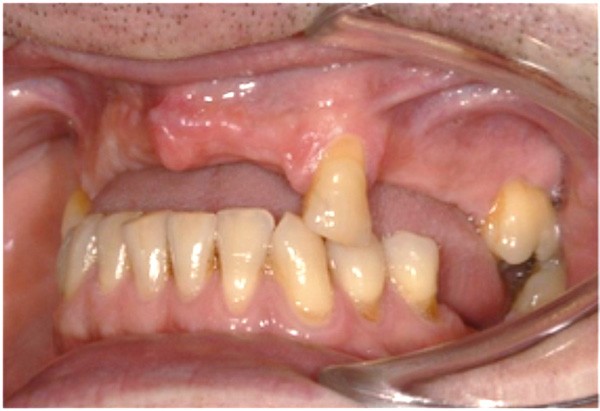

Le deuxième volet de la conférence traitait des ostéotomies segmentaires au cours desquelles un segment d’os alvéolaire (avec ou sans les dents) est déplacé. Cette technique chirurgicale consistant à libérer un segment plus ou moins étendu du prémaxillaire assure la reconstitution du capital squelettique dans le sens vertical et sagittal respectivement à l’aide des greffes simultanées d’interposition et d’apposition.

Cette partie de la présentation ne se contentait pas de rapporter les principes précédemment décrits à des régions limitées des maxillaires mais étendait la discussion à la difficulté majeure rencontrée en implantologie : rattraper des erreurs de positionnement implantaire ayant entraîné des compromis prothétiques inesthétiques. La solution thérapeutique mise en œuvre par Benoît Philippe consiste à appliquer la procédure d’ostéotomie segmentaire à l’entité constituée par l’os alvéolaire péri-implantaire et les implants. Les couronnes implantaires sont déposées. Le tracé d’ostéotomie encadre le segment à repositionner mais n’implique pas la corticale palatine qui sera fracturée pour éviter toute lésion du périoste (nourricier du segment alvéolo-implantaire). Un dispositif prothétique préparé en amont guide la translation du fragment qui est fixé au moyen de plaque d’ostéosynthèse dans la situation idéale. Le capital squelettique est reconstruit et l’espace prothétique disponible est normalisé.